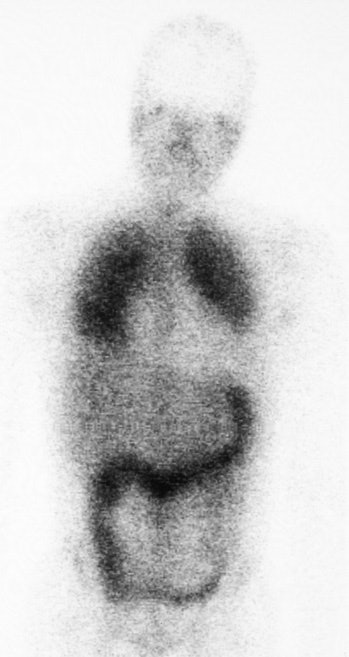

PCP on Ga-67 exam

Ga-67 exam in an HIV patient with PCP pneumonia demonstrates diffuse homogeneous increased accumulation of the tracer within the lungs bilterally. Increased uptake within the colon is related to an underlying colitis.